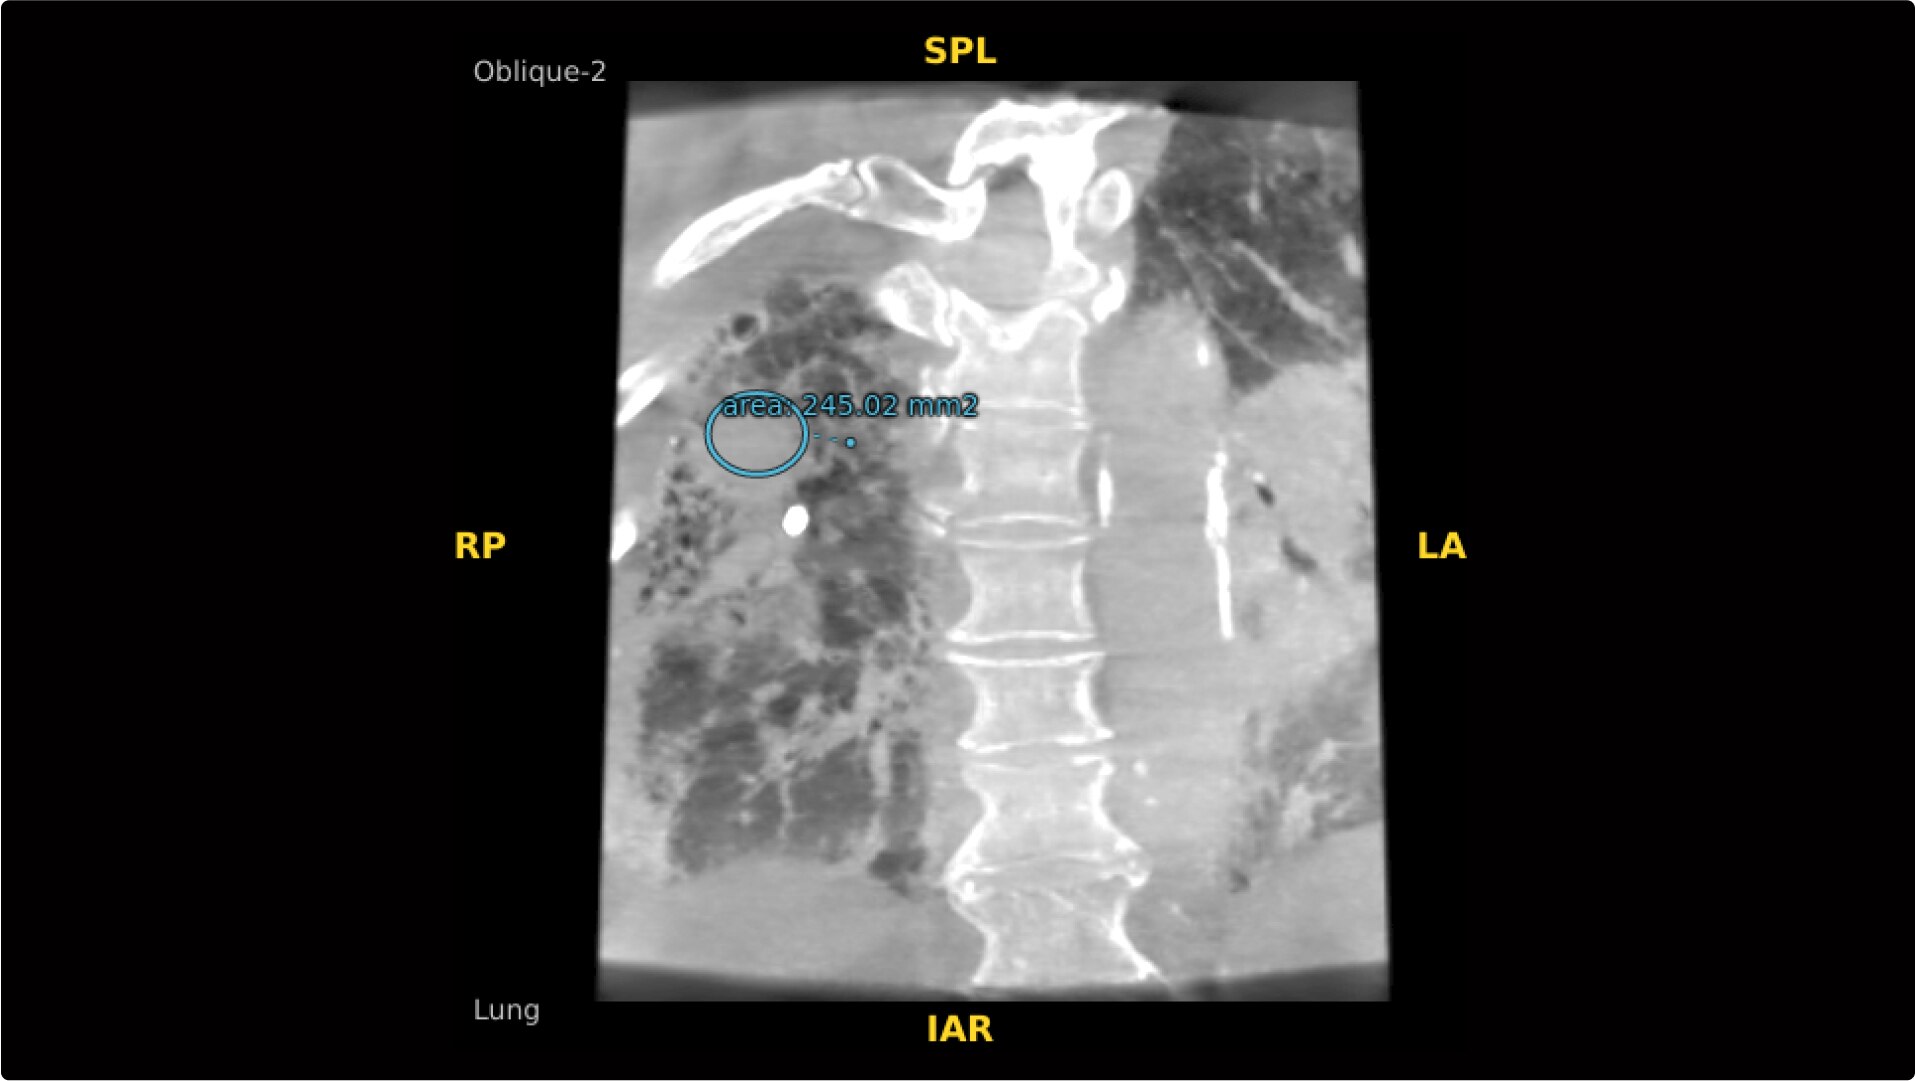

Select Lung Preset for optimized view of pulmonary structures. Easily change slices or adjust slice thickness for multiplanar assessment of lesions and bronchial structures.

Analyze CT-like images with the OEC 3D Volume Viewer which includes Multi Oblique Mode with reference coordinates, Window Level/Window Width, rotate, zoom, and more for quick and comprehensive tool-in-lesion confirmation.